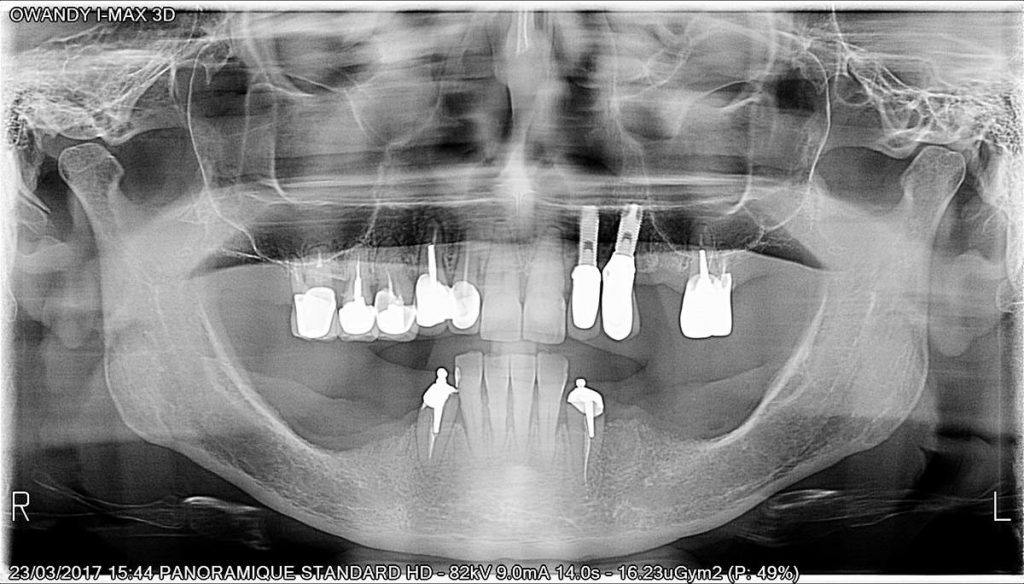

Calidad de imagen excepcional